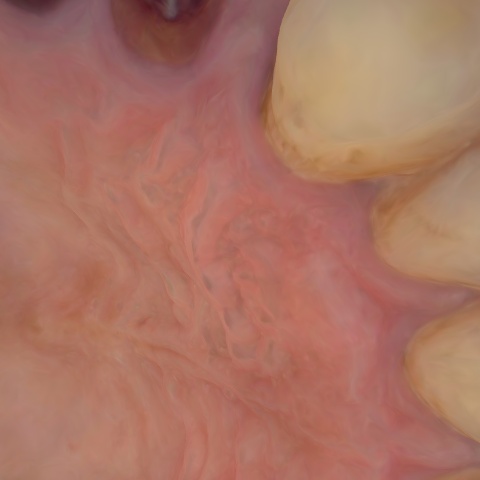

Annotated as "Good"